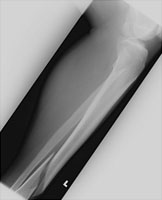

Tibial Shaft Fracture

Fractures of the shaft of the tibia are due to direct trauma. This particular fracture is spiral in nature. More comminuted fractures of the proximal tibia may compromise blood supply of the popliteal artery, and angiography may be considered.

- Click on the image for a larger versionAAP radiograph of the tibia and fibula. There is a spiral fracture of the tibia.